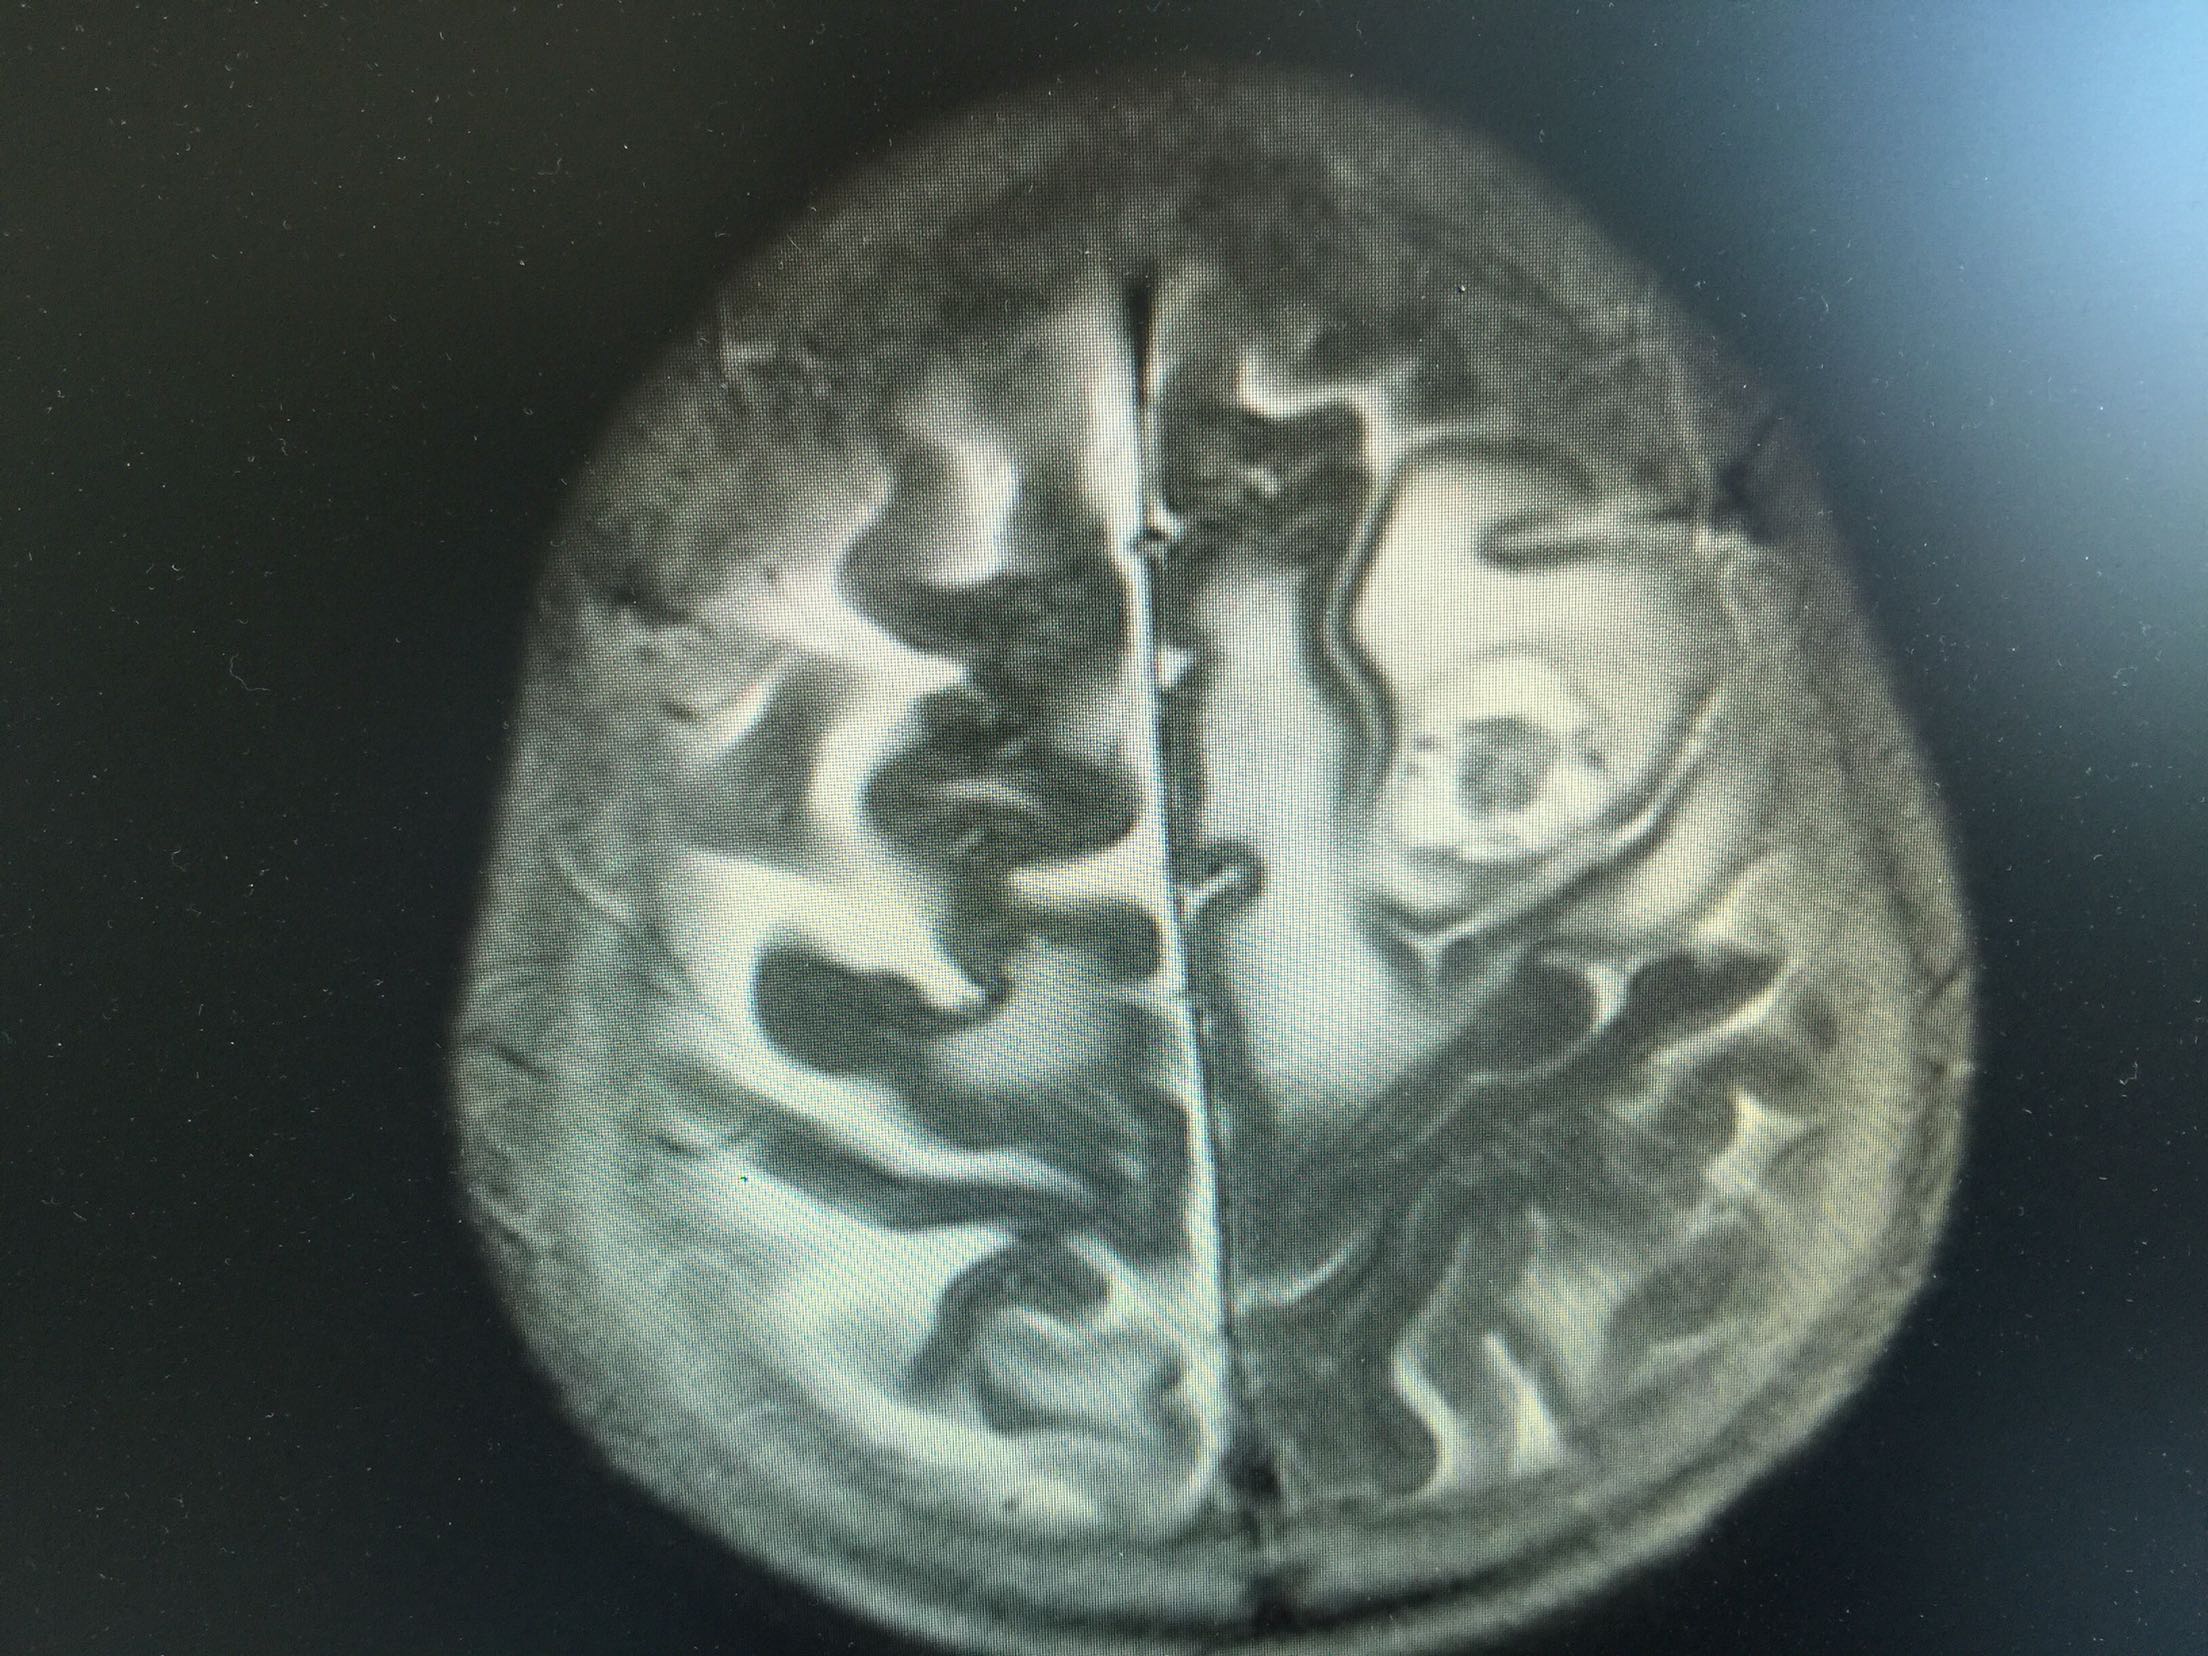

1.女,81岁,以“右侧肢体无力3天”入院。 2.现病史:3天前无诱因出现右侧肢体无力,右上肢抬举费力,右下肢步行拖拉,无抽搐,无意识障碍! 3.既往史:2016年肺穿刺活检,免疫组化为腺癌!已合并第五、六椎体转移、左肾上腺转移,行灌注介入治疗。

左肺腺癌 骨转移、双肺门及纵膈淋巴结转移、左肾上腺转移、脑转移! 治疗:对称、支持治疗!